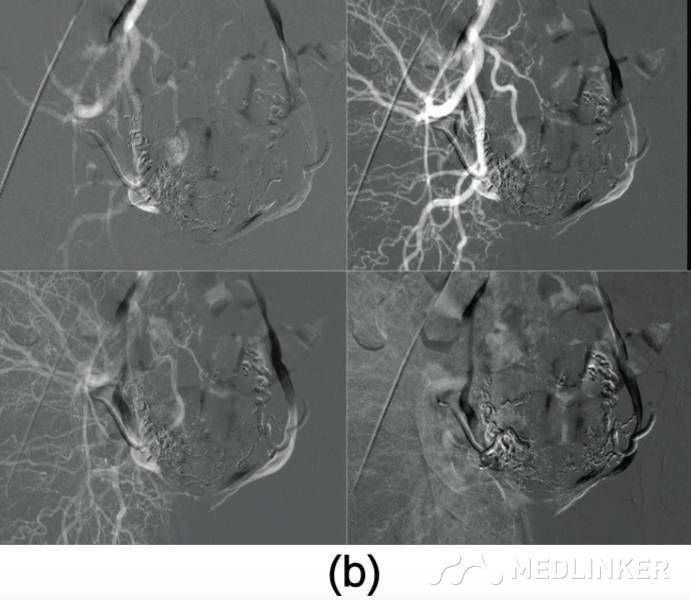

患者入院诊断:动静脉畸形。介入科会诊后行双侧子宫动脉栓塞术,栓塞材料为氰丙烯酸丁酯和碘油的混合物。该患者栓塞前后情况如图2所示。子宫动脉栓塞术后,患者未出现并发症,术后2天,患者出院,血hCG降至1766mIU/mL。术后1个月复查超声,未见血流,且受损范围缩小至61∗46∗52mm(77cm3)(图3),血hCG<0.5mIU/mL。  图2(a)右/左髂内子宫动脉造影术示:轻度扩张的子宫动脉显影浑浊,子宫内见多血管性肿块;(b)双侧子宫动脉栓塞术后图像   图3(a)2个月后的阴式超声示::受损范围缩小至61∗46∗52mm(77cm3);(b)多普勒彩超未见血流              根据年龄、生育要求、病变位置及范围大小选择不同的治疗方案,AVM主要的治疗方法是子宫切除和子宫动脉栓塞。育龄期有生育要求的子宫动静脉瘘患者首选治疗方法是子宫动脉栓塞,但是其远期的安全性尚存争议,而且行子宫动脉栓塞术后,妊娠的孕妇发生胎位异常、早产、产后出血及剖宫产的风险增大。        一些学者认为保守治疗适合无症状的AVM患者;还有学者认为出血少的AVM患者可以用甲基麦角新碱、促性腺激素释放激素类似物、达那唑等治疗。总之,目前对无症状的子宫动静脉瘘的治疗暂无统一的共识。        总之,子宫动静脉瘘是比较罕见且危险的临床疾病。通常,这种疾病常见于既往发生过自然流产的年轻女性,我们应该牢记行人工流产术(吸宮术)的患者,术后可能会继发子宫动静脉瘘,同时应该注意该病与其他疾病的鉴别。